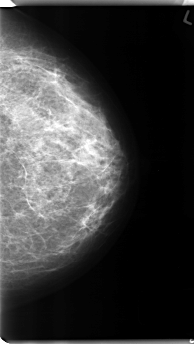

C_0136_1.LEFT_MLO

RIGHT_MLO LINES 4688 PIXELS_PER_LINE 2656 BITS_PER_PIXEL 12 RESOLUTION 50 NON_OVERLAY